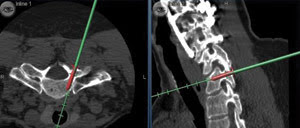

Functional Imaging & MRI

The National Cancer Institute estimated that 1,437,180 people would be diagnosed with cancer in 2008 and that 565,650 people would die of the disease. Cancer research is, of course, ongoing, and recent decades have seen great strides in our...